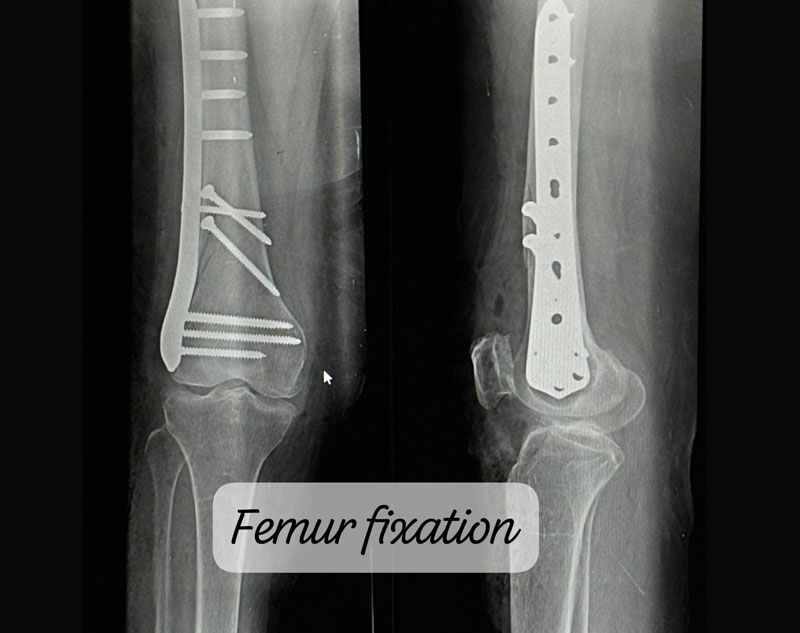

Treatment for complex trauma requires a multidisciplinary approach, including surgical intervention, internal/external fixation, and sometimes reconstruction of damaged tissues.